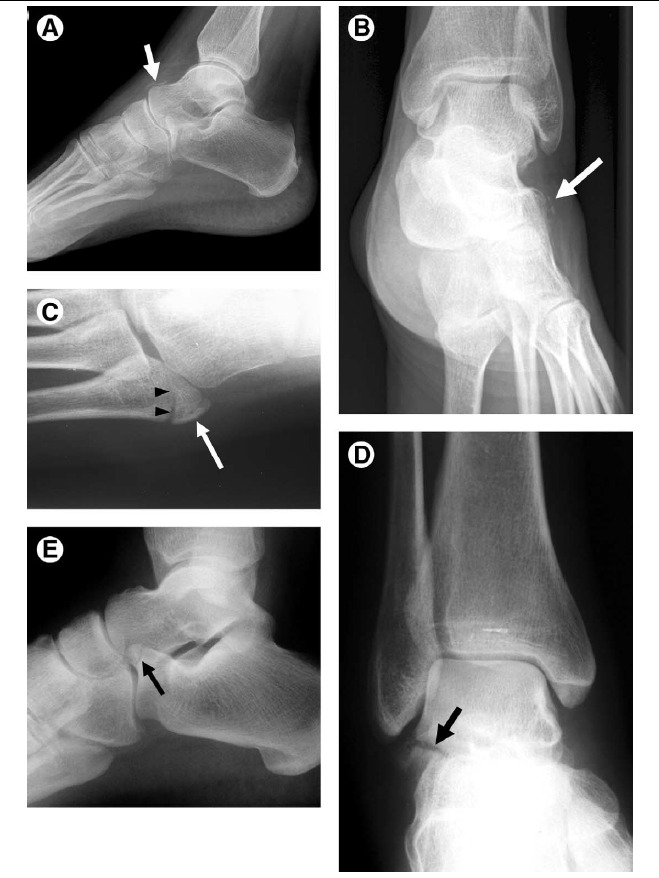

Figure 5 Fractures associated with ankle sprain. Avulsion fractures, particularly at the lateral malleolus, are common in the

setting of ankle sprain. Occasionally overlooked are sites of other fractures, including the following.

(A) Dorsal capsular avulsion. Lateral view of the foot demonstrates a curvilinear calcification dorsal to the talar head (arrow) representing a capsular avulsion. These may also occur at the navicular bone.

(B) Extensor digitorum brevis avulsion. Oblique view of the ankle shows thin calcification (arrow) adjacent to the anterolateral calcaneus consistent with an avulsion fracture from the origin of the extensor digitorum brevis tendon.

(C) Fifth metatarsal base fracture. AP view of the fifth metatarsal base in a skeletally immature patient shows a longitudinally directed, rounded ossification center (arrow) as well as a transversely directed avulsion-type fracture (arrowheads). Avulsion-type fractures in this location typically extend to the tarsometatarsal articular surface, whereas Jones-type fractures are more distal, occurring at the proximal shaft.

(D) Lateral talar process fracture. A fracture of the lateral talar process (arrow), also called a “snowboarder’s fracture,” is seen on this AP view of the ankle. These fractures are commonly missed and can be a source of chronic pain after a severe ankle sprain.

(E) Anterior process fracture of the calcaneus. Lateral view of the ankle shows discontinuity of the anterior calcaneal process (arrow). Like the snowboarder’s fracture, this injury is often missed on initial eval‎uation, resulting in chronic pain.